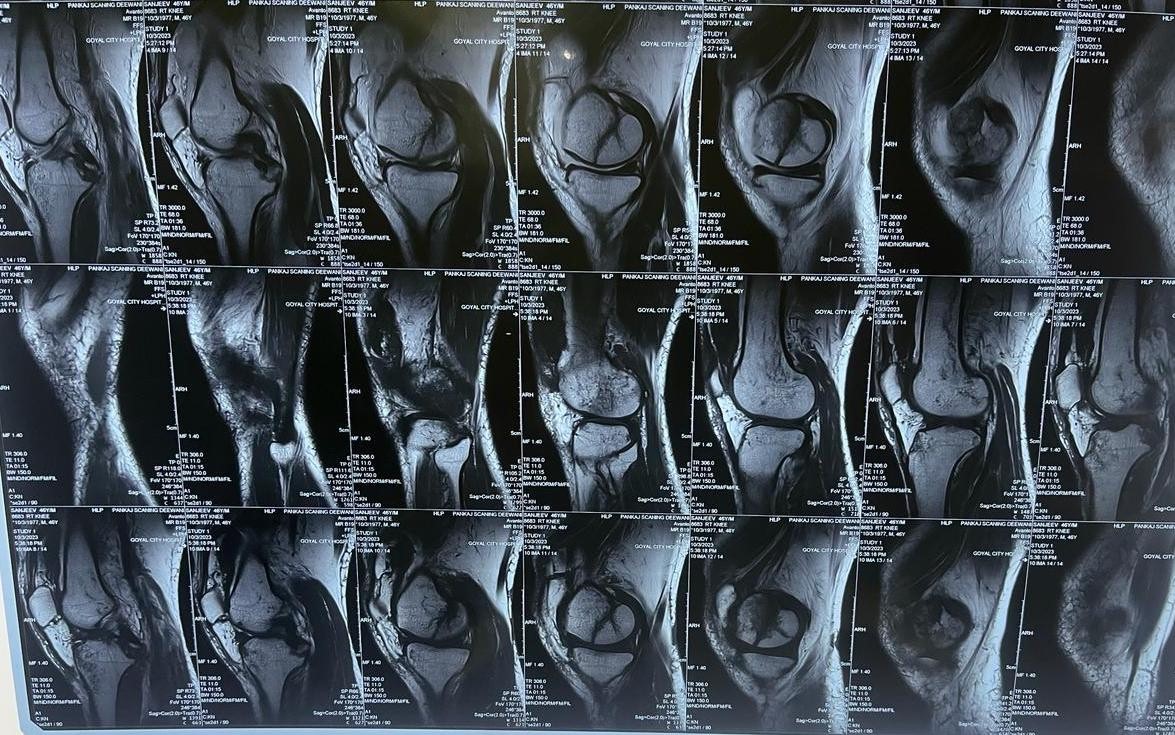

Magnetic resonance imaging (MRI) scan was performed to better delineate the associated other ligaments and chondral injuries (Fig. 2).

Figure 2: Pre-operative magnetic resonance imaging sagittal images showing posterior cruciate ligament avulsion fracture with Hoffa fracture.